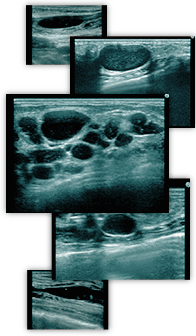

THE CLINICでは、このような他院で受けたヒアルロン酸注入の豊胸によるしこりのお悩みに対応すべく、乳腺用エコーを使用し、しこりを目視しながら確実に除去する治療法を採っております。

ただし、ヒアルロン酸注入後にしこりに気付いたとしても、それがヒアルロン酸のしこりとは限りません。そのため、まずは乳腺用エコーできちんと検査、診断することが大切です。